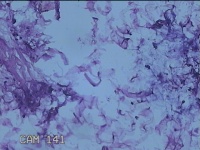

性别

女

年龄

36岁

临床诊断

皮肤良性肿瘤

发现左侧大腿息肉组织2年余,无明显疼痛及不适。

左侧大腿息肉组织

大体所见

灰白粉红色息肉样组织4.3x3.3x0.8cm一块,表面光滑,切开组织呈实性,切面灰白粉红色,质软。

图2